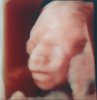

Młody ma się dobrze, dosłownie wsio okej, więc nie wymieniam, nawet dość ładnie buziaka pokazał do zdjęć, nasze małe ufo